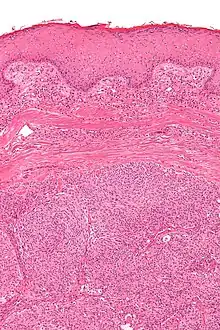

| Micrograph showing an acrospiroma. H&E stain. | |